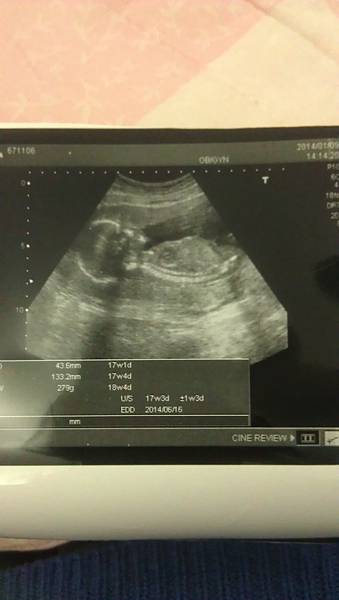

話說第一次產檢時大概是7周吧

那時就可以聽見寶寶的心跳聲囉

講到第17周到20周間他說這時候你要做羊膜穿刺歐